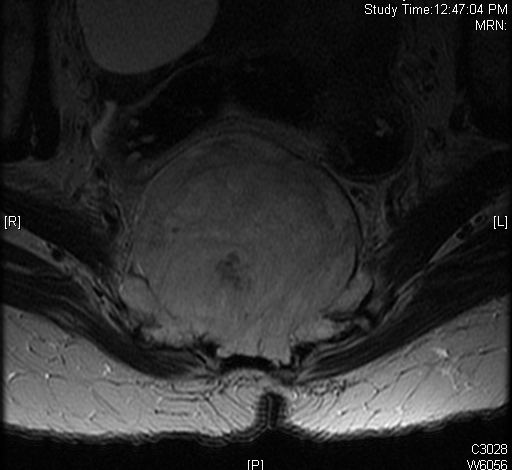

MRI (Fig. 4-10)

• Hyperintense on T2W (Fig. 8 & 9)

• Hyper enhancement with gadolinium (Fig. 6 & 7).

Fig. 4-10: MR image of a chordoma shows a destructive bone lesion in the sacrum that is hypointense on T1W images, hyperintense signal on T2W and enhancement of the lesion after gadolinium.